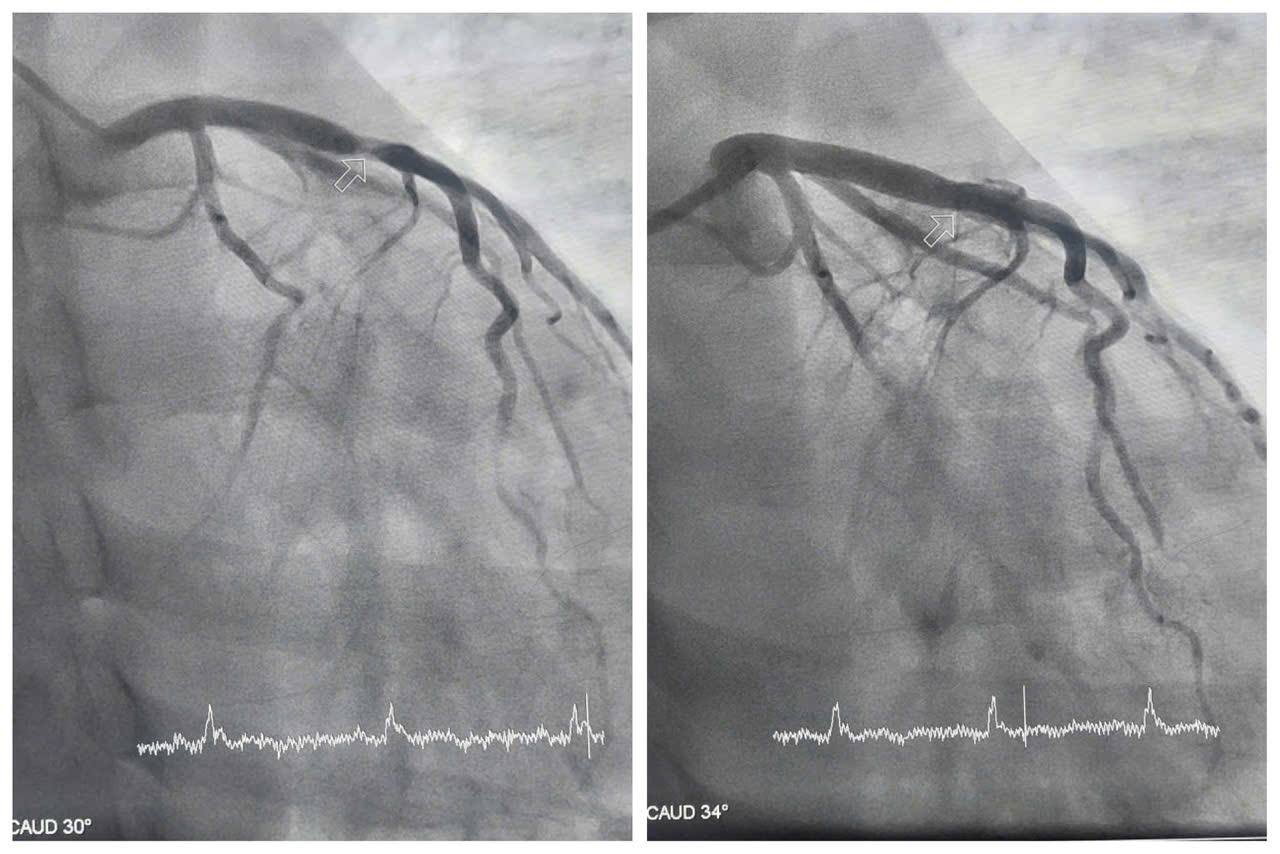

Bệnh nhân nhanh chóng được chuyển phòng can thiệp chụp mạch vành kiểm tra. Kết quả chụp cho thấy động mạch liên thất trước - một trong những nhánh mạch vành quan trọng nuôi dưỡng cơ tim, bị tổn thương nặng, hẹp khít 99%. Trước tình trạng nguy hiểm, các bác sĩ khoa Phẫu thuật và Can thiệp Tim mạch thực hiện can thiệp đặt stent nhằm tái thông máu nuôi tim, giúp người bệnh thoát khỏi tình trạng nguy hiểm.

Hình ảnh hẹp tắc động mạch liên thất trước của bệnh nhân H. được can thiệp tái thông